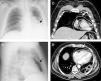

A 50-year-old man presented to the emergency department with three-day progressive worsening of dyspnea. His medical history included poorly differentiated stage IV epidermoid lung carcinoma, under palliative chemotherapy. On admission, he was hemodynamically stable, with no signs of respiratory distress. There were no significant abnormalities on laboratory or blood gas analysis. The chest X-ray (Figure 1A and B) showed a radiolucent band of air partially surrounding the heart. Thoracic computed tomography (Figure 1C and D) confirmed the presence of pneumopericardium. Air in the pericardial space made acquisition of transthoracic echocardiographic images impossible (no echocardiographic window). The patient did not present clinical manifestations of cardiac tamponade, so conservative treatment was decided on. He improved clinically and was safely discharged to the outpatient palliative care clinic after one week. At one-month follow-up, the patient was asymptomatic with no evidence of residual pneumopericardium on the chest X-ray.

Chest X-ray on admission showing a radiolucent band of air partially surrounding the heart (arrows) consistent with pneumopericardium, in posteroanterior (A) and lateral (B) views; chest computed tomography scan confirming the presence of pneumopericardium (arrows), in coronal (C) and axial (D) views.